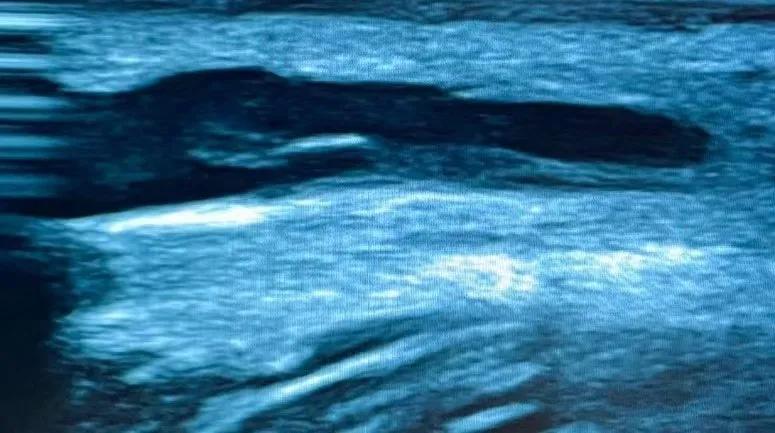

老渠多年糖尿病史,反复长期输液,术前评估发现其左上肢桡动脉尺动脉纤细,头静脉及肘正中静脉匮乏,头静脉前臂中段处有一处严重内膜损伤(见图1),桡动脉4.2mm,肱动脉分叉位于肘上,上臂贵要静脉束臂后2.8mm。右上臂头静脉条件略好,但肘上6cm处有一处内膜损伤,可能会影响内瘘成熟。经过详细的术前评估后,张东亮主任医师决定为患者行“左上肢桡动脉-贵要静脉人工动静脉内瘘血管转流”。这样既能绕开内膜损伤处,又可以为内瘘使用提供更多穿刺空间。

图1 超声提示静脉内膜损伤增生